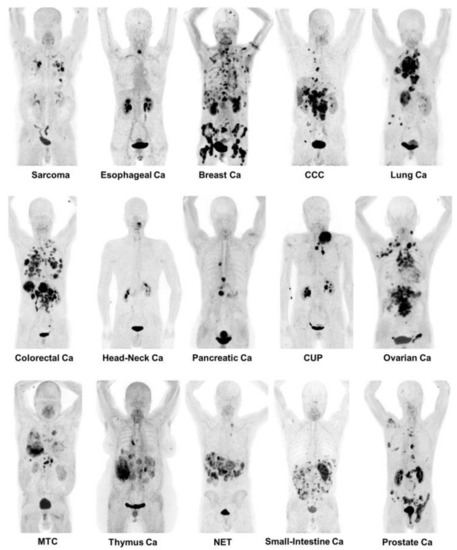

- Kratochwil, C.; Flechsig, P.; Lindner, T.; Abderrahim, L.; Altmann, A.; Mier, W.; Adeberg, S.; Rathke, H.; Röhrich, M.; Winter, H.; et al. 68Ga-FAPI PET/CT: Tracer Uptake in 28 Different Kinds of Cancer. J. Nucl. Med. 2019, 60, 801–805. [Google Scholar] [CrossRef] [Green Version]